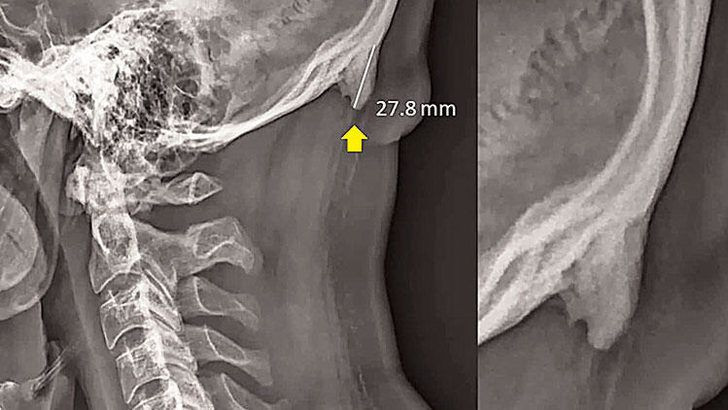

Avustralya’daki Sunshine Coast Üniversitesi’den Dr. David Shahar ve Prof. Mark Sayers isimli iki bilim insanının, 18-30 yaş arasındaki 218 kişinin röntgen çekimlerini inceleyerek yürüttüğü araştırmada, bu kişilerin neredeyse yarısının kafatası şeklinin yoğun cep telefonu ve tablet kullanımına bağlı olarak ‘değiştiği’, boynuzumsu bir çıkıntıya benzediği belirtildi.

Araştırmaya göre, gününün büyük kısmında teknolojik aletlere kafasını eğerek bakan gençlerin, kafatasındaki oksipital kemik denen bölge, görünür şekilde belirginleşmeye başlıyor. Her 4 gençten birinde görülen bu durum, dijital ekranlar karşısında geçirilen süreyle ilgili endişelere bir yenisini daha ekliyor.

10 yıldır gözlemleniyor

Bilim insanı Shahar, 20 yıldır klinik tedavi uzmanı olduğunu belirterek “Ancak sadece son 10 yıldır hastalarımın kafatasındaki büyümeyi gözlemliyorum” dedi. Ensenin üstünde sivrilen 10-30 milimetre arasında değişen çıkıntıya, ‘dış oksipital kabartı’ deniyor.

Dış oksipital kabartıya, taşınabilir dijital cihazlar yaygınlaşmaya başlamadan önce daha çok yaşlı insanlarda rastlandığı, gençlerde ise oldukça nadiren rastlandığı belirtiliyor. Kafatasındaki çıkıntının, iskelet yapısında uzun süre baskıya maruz kalmış kişilerde rastlanması hesaba katıldığında, uzun süre cep telefonu ekranına bakmanın da benzer etkiyi yarattığı söylenebilir.